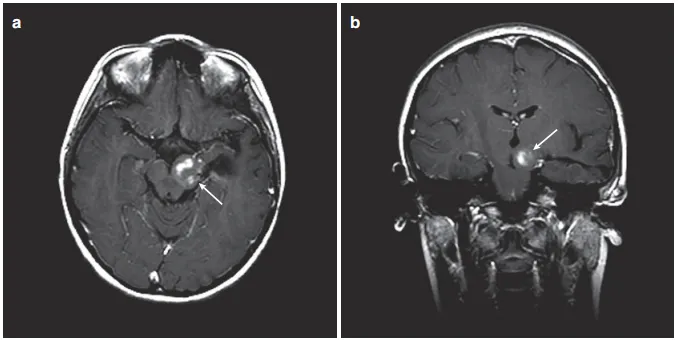

图3:患儿术后MRI,(a)轴位增强MRI显示肿瘤少量残留在左侧被盖。(b)冠状MRI对比显示从颞中回至中脑肿瘤的少量残余肿瘤。